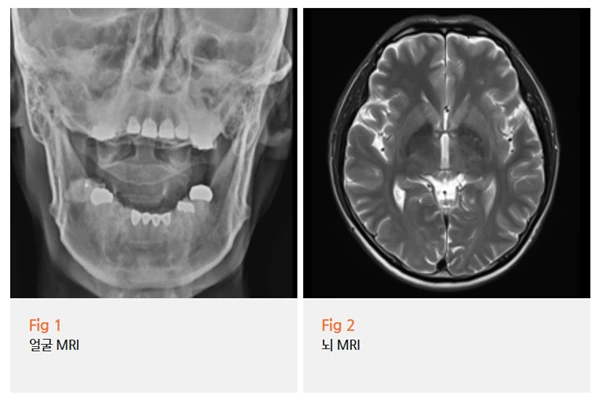

저희는 환자분께 먼저 뇌 MRI 검사를 권유드렸습니다.

삼차신경통과 유사한 증상을 보이는

다른 뇌 질환을 감별하기 위해서는

영상 검사가 꼭 필요하기 때문이에요.

다행히 뇌 MRI 검사 결과, 뇌종양이나 뇌졸중 같은

기질적 이상은 확인되지 않았습니다.

하지만 삼차신경 주변의 혈관 주행이

신경과 근접해 있는 양상이 관찰되었고,

환자분의 임상 증상과 종합했을 때 삼차신경통으로 진단할 수 있었습니다.

MRI 결과를 보여드리며 자세히 설명을 드렸더니,

환자분은 그제야 안심하신다는 표정을 지으셨어요.

치과에서 이상 없다는 말만 들으면서

본인이 이상한 건가 싶어 불안하셨는데,

명확한 원인이 있다는 걸 알게 되니

마음이 훨씬 편해지신다고 하셨습니다.